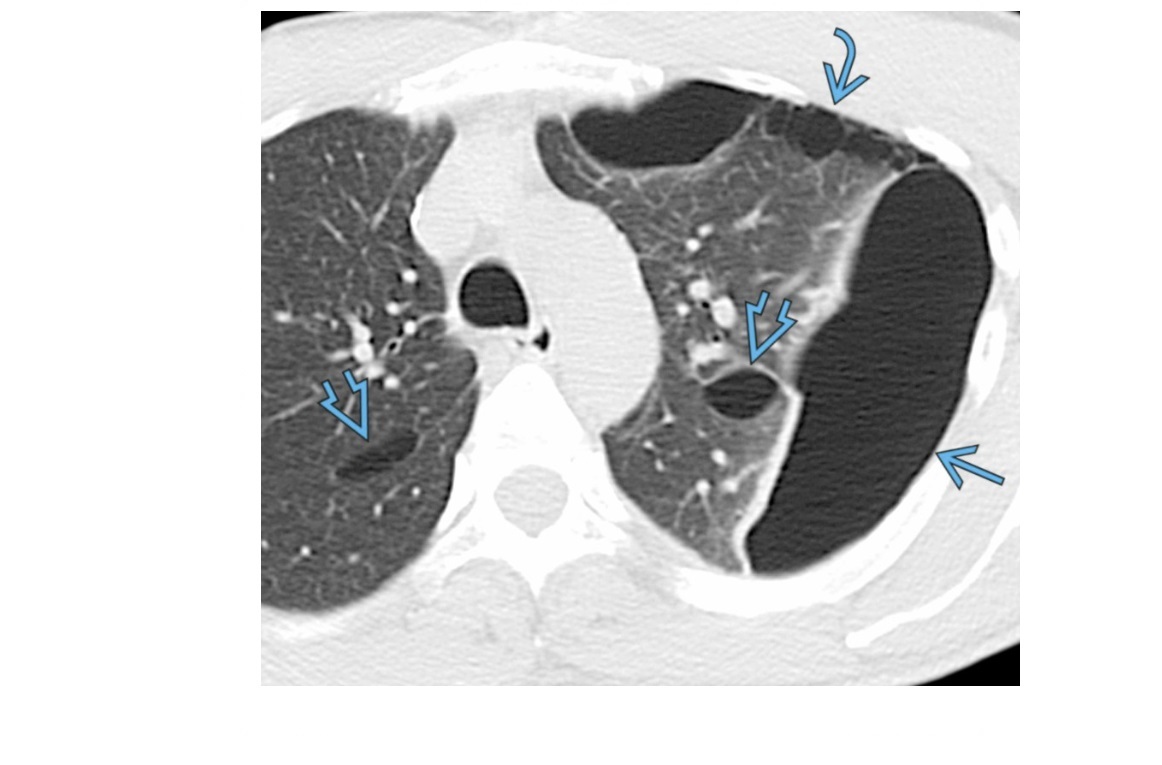

UIP

CXR

Reticular or reticulonodular opacities

Subpleural/peripheral; mid and lower lung zones

Macrocystic Honeycombing (strongest predictor)

Basilar predominant

Traction bronchiectasis

Subpleural reticulations

smoking association

Causes

- connective tissue disease such as RA

- asbestosis

- Drugs (amidorane, nitrofurantoin, methotrexate)

- IPF (diagnosis of exclusion)